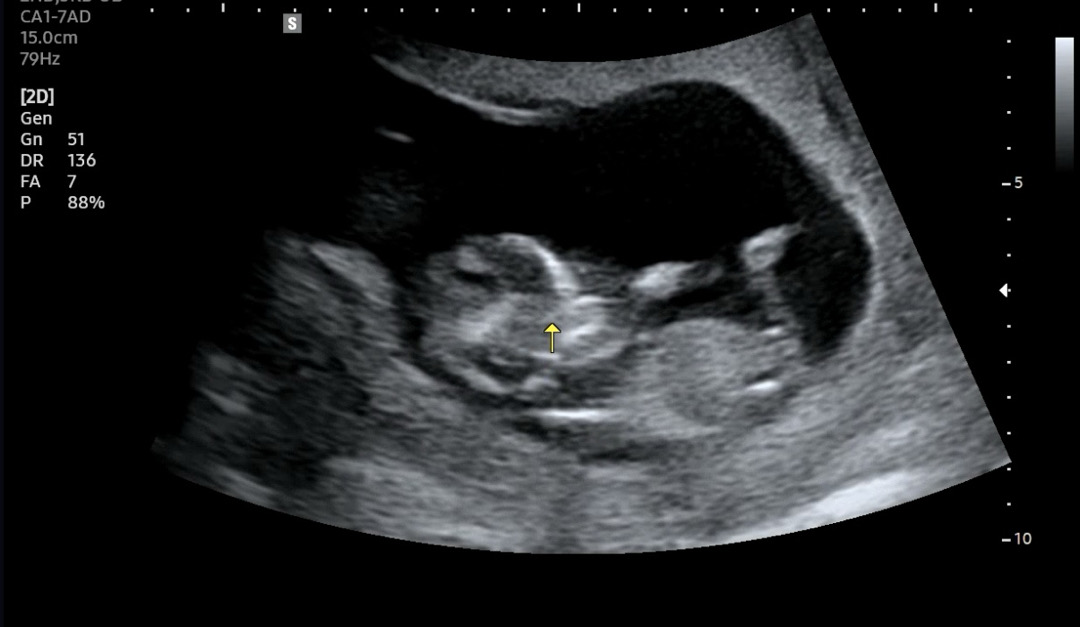

12주 각도법 봐주실 수 있을까요🥹🫶

너무 궁금해요><

니프티 결과 정말 딸이 나왔네요! 너무 신기해요😆